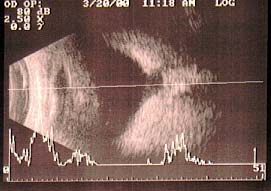

À Ultrassonografia pode-se observar condensações vítreas e aumento grande da escavação papilar deslocada posteriormente.

Ultrassonografia olho esquerdo